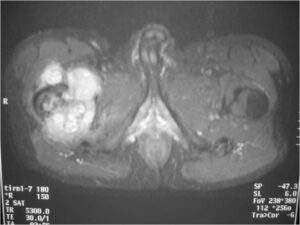

Sites:

- Most common in pelvis, proximal femur, proximal humerus, distal femur, ribs

Radiographic Presentation

Radiology emulates pathology: Biphasic Tumor

- One region low grade chondrosarcoma

- Second more aggressive area with bone destruction, lysis of calcification, soft tissue mass

- Cortical permeation and a soft tissue mass in 70% of cases

Ill-defined, lytic intraosseous lesion

- Or extraosseous soft tissue mass

- Devoid of calcifications in continuity with lesions having the features of a cartilaginous tumor

Characteristically abrupt transition between chondroid tumor and dedifferentiated, lytic component

Bone may be expanded and adjacent cortex thickened

Biological Behavior

- Very aggressive locally

- Frequently cortical perforation

- Mass is usually large if extraosseous extension occurs